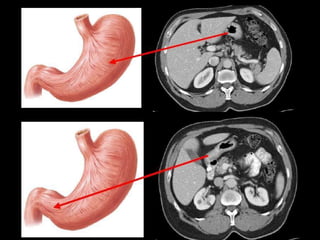

WITHOUT CONTRAST STOMACH COLON UPPER GIORAL BARIUM CONTRAST. BARIUM ENEMA.